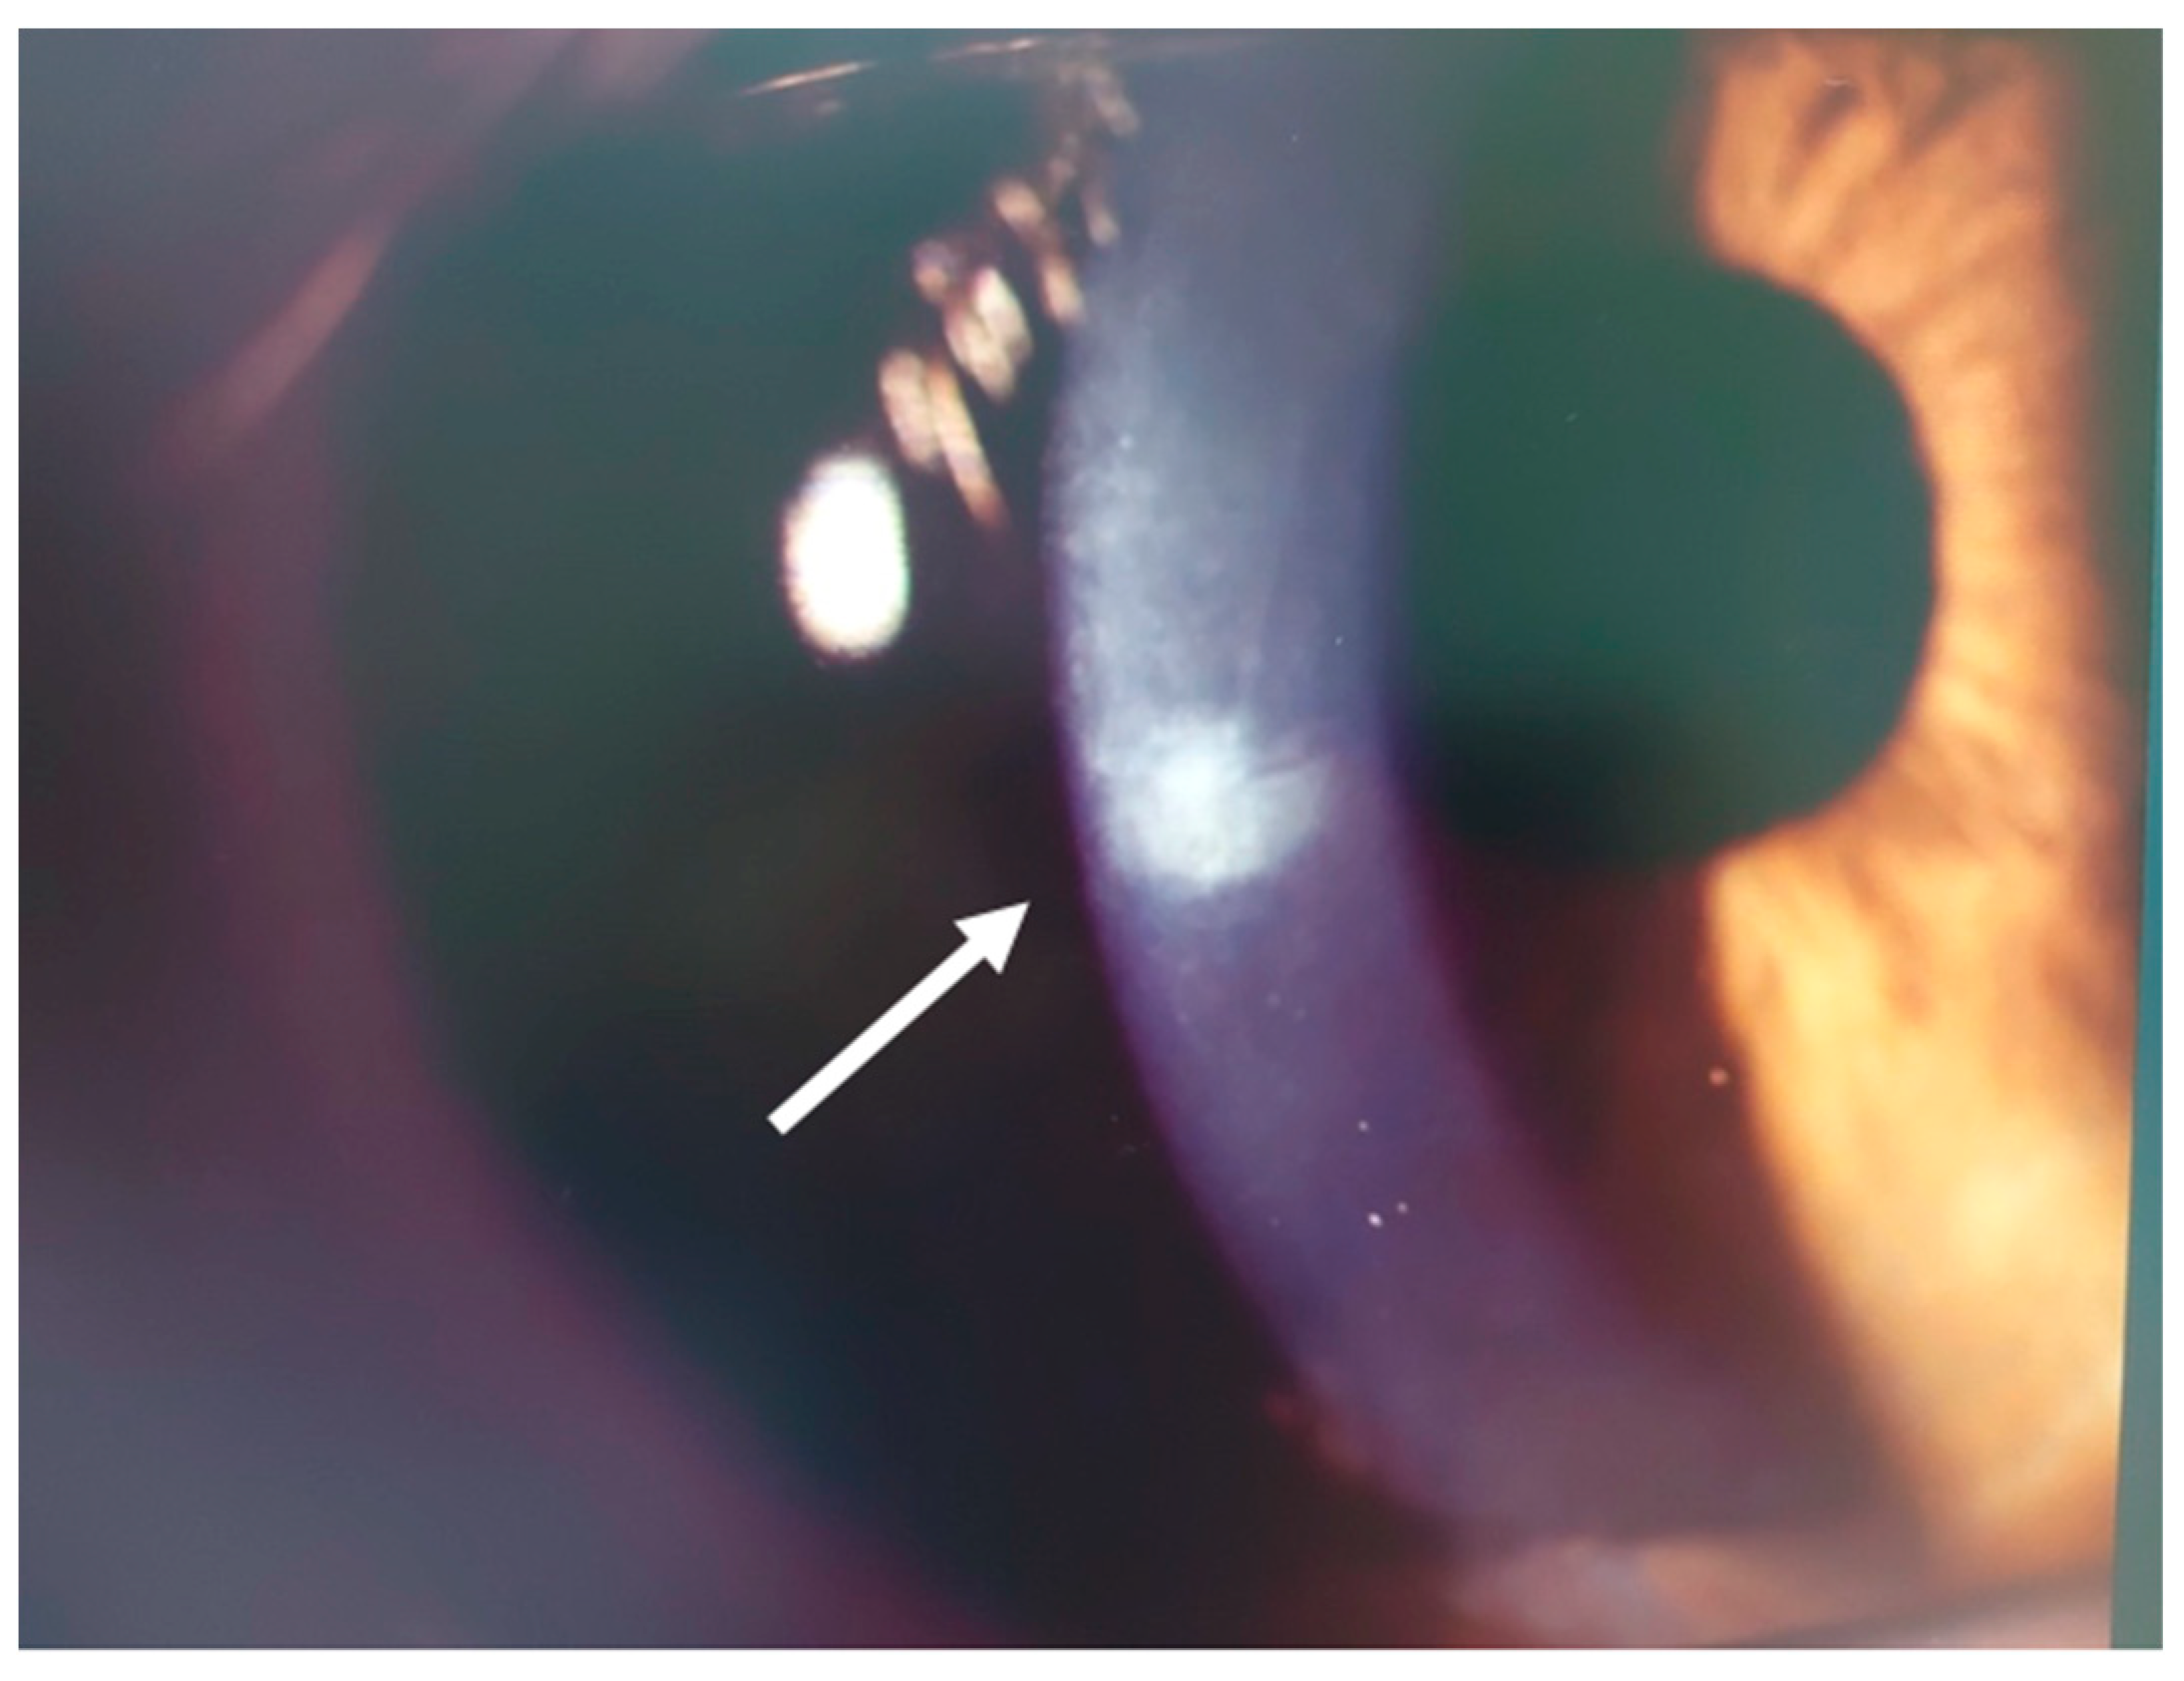

3.1. Patient #1